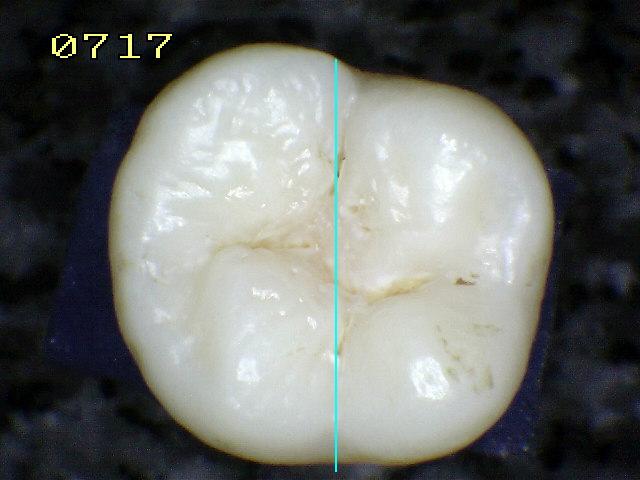

Espécimen Nº

41 |

Código histológico 1 |

Espécimen Nº 32 |

|

Corte sagital |

Código 2 histológico